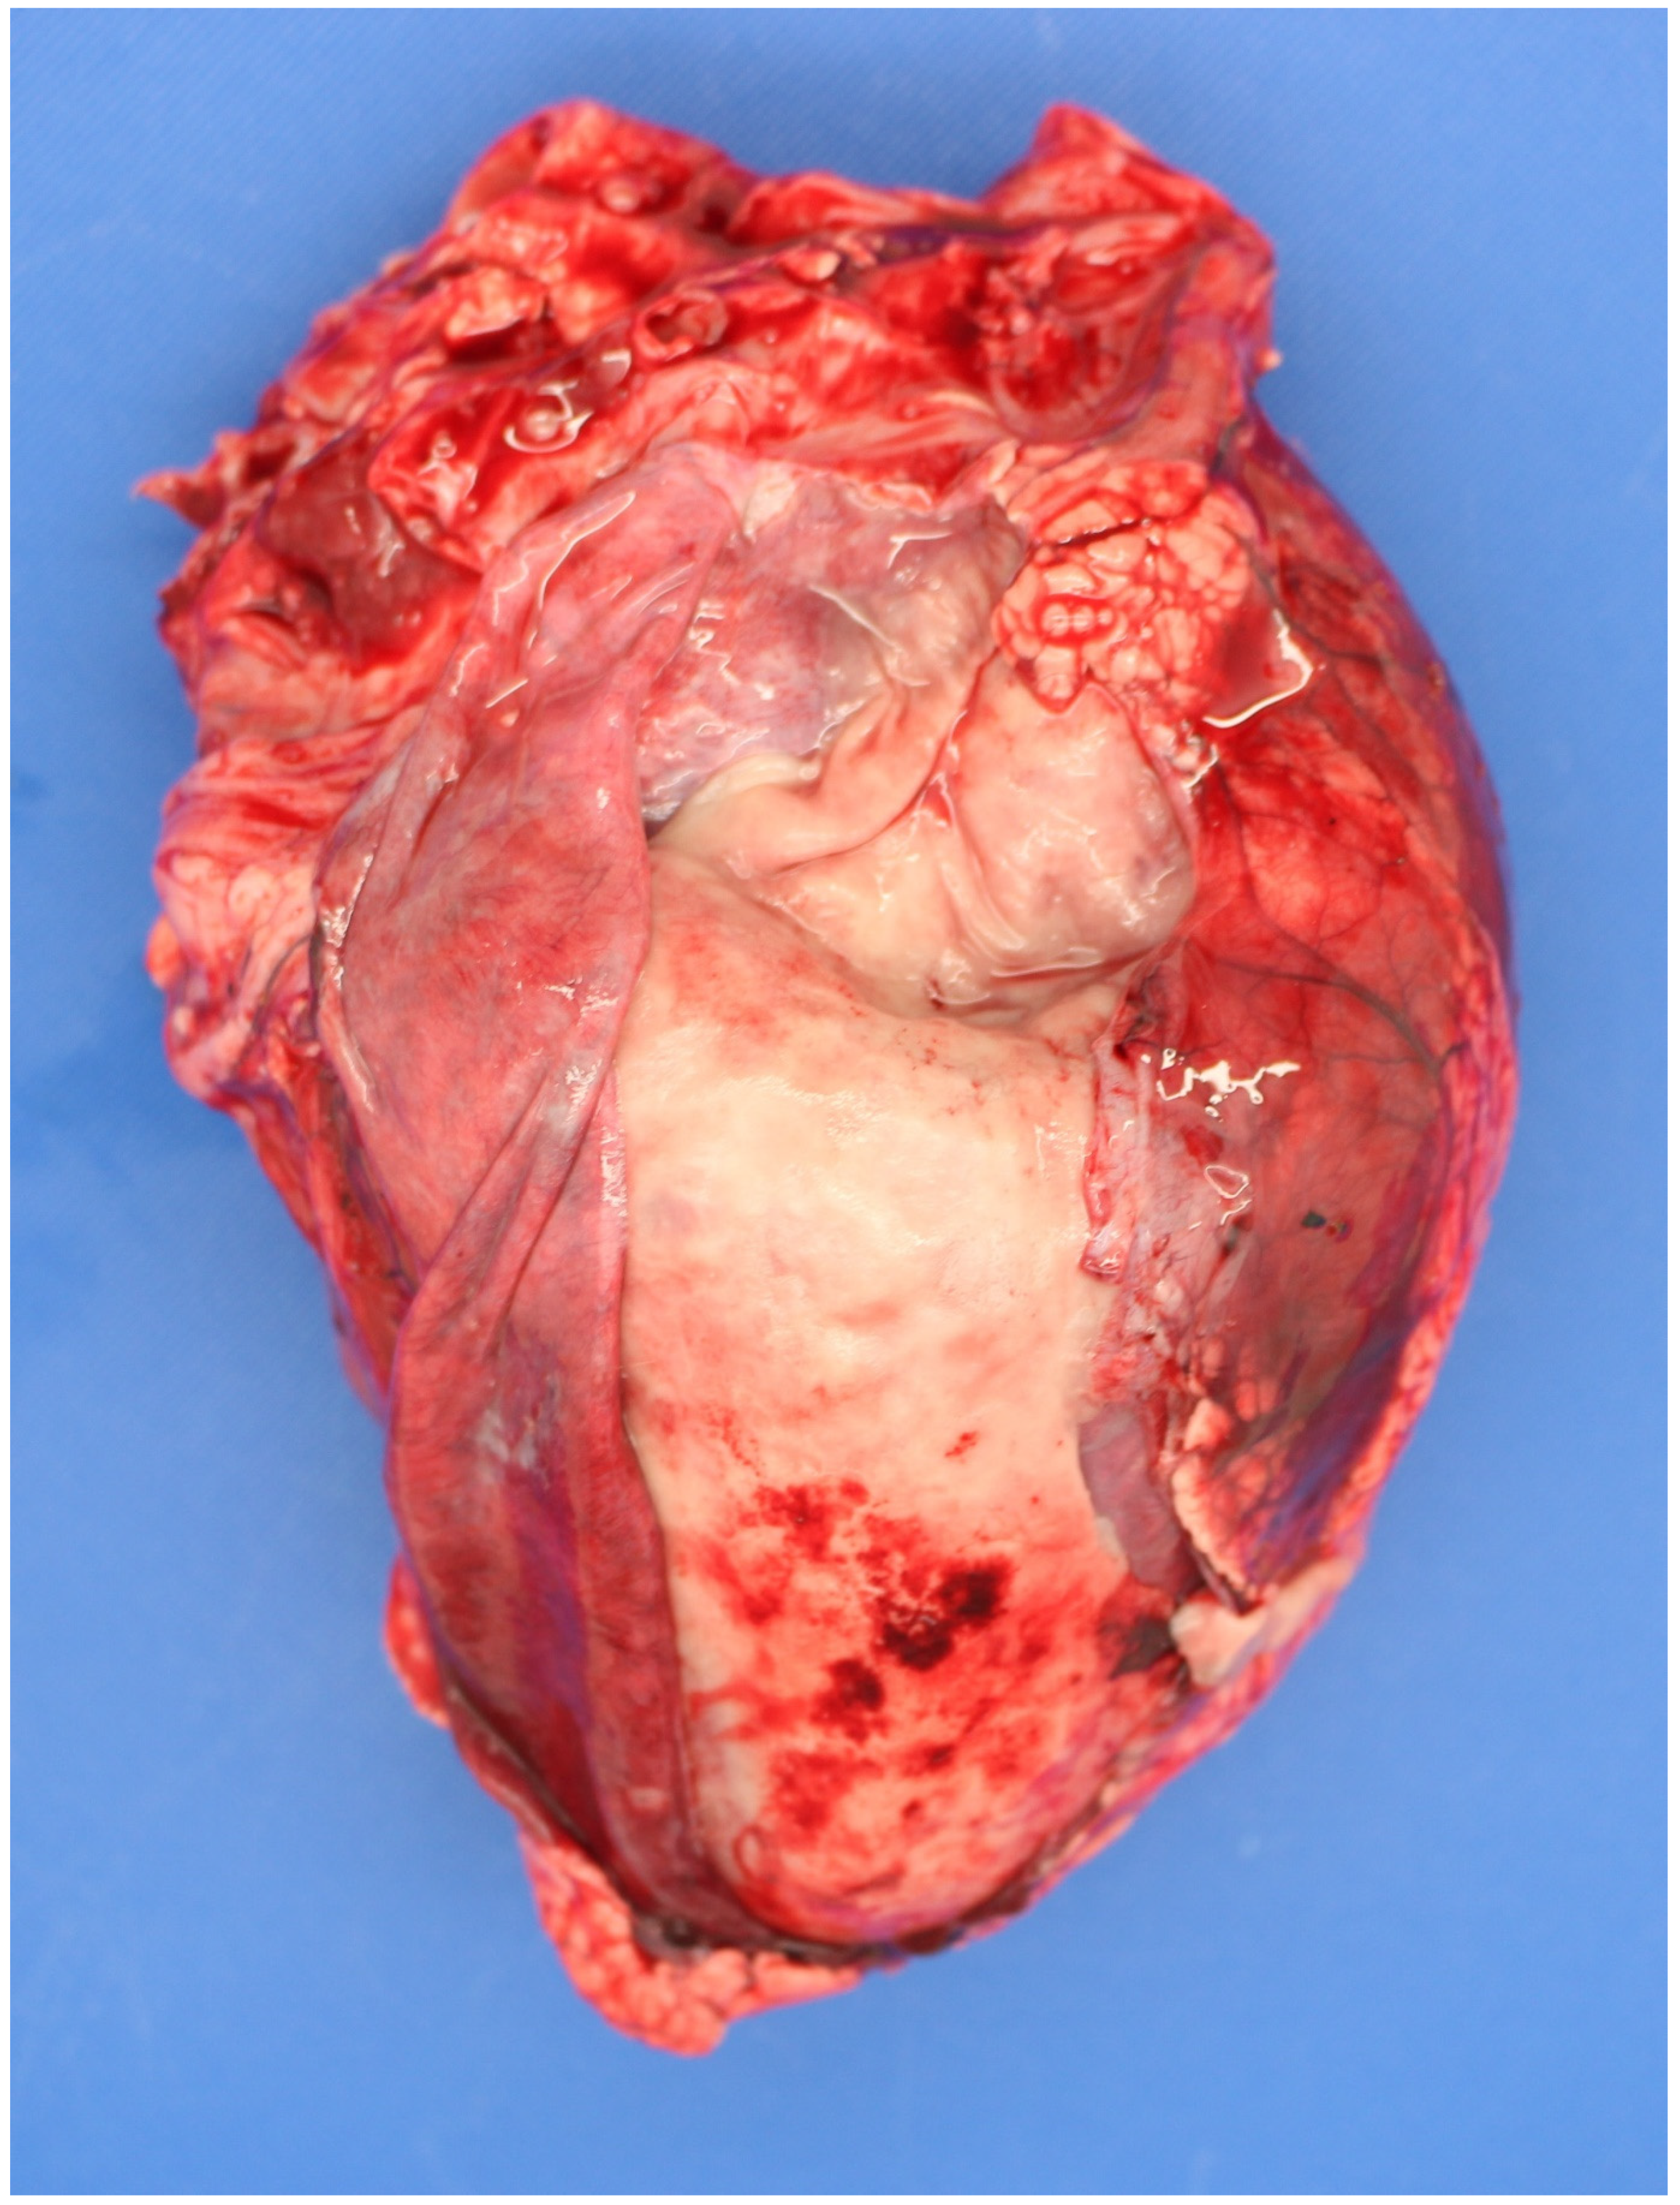

3.5. Examination of the Placenta

| Neospora caninum | Foetal brain, serum | Foetal heart. Placenta. Dam/cohort bloods | Fresh brain/placenta for PCR, fixed brain or heart/placenta for histopathology if PCR positive |